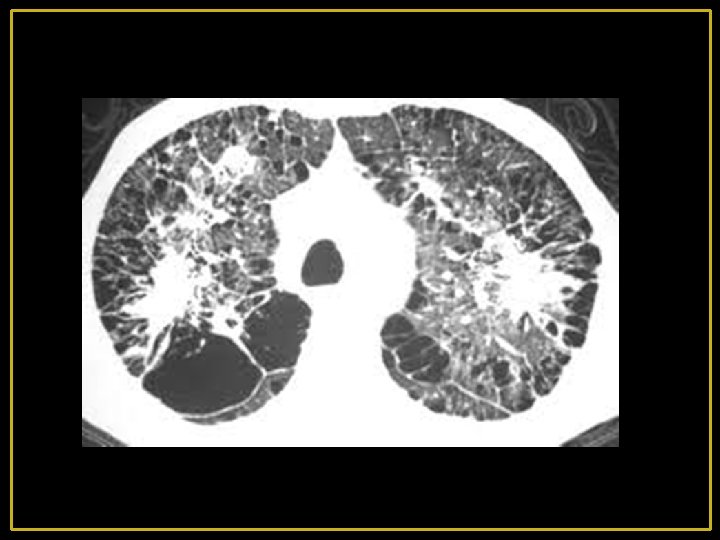

On distingue 4 types d’emphysèmes selon la localisation des lésions dans l’acinus : 1 - Emphysème panlobulaire: (Pan-acinaire) : EPL C’est l’ensemble de l’acinus qui est touché associé à des lésions vasculaires avec fenestration puis destruction de leurs parois et confluence des espaces aériens distaux. Il s'agit d'un emphysème diffus prédominant aux lobes inférieurs. Ce type d’emphysème est retrouvé chez les patients porteurs d’un déficit en α 1 antitrypsine, les sujets âgés non-fumeurs et les fumeurs sans déficit en α 1 antitrypsine. 2 - Emphysème centrolobulaire(centro-acinaire) ECL Les lésions sont retrouvées en position centrale de l’acinus alors que les alvéoles sont préservées. L’atteinte prédomine souvent dans la partie supérieure des lobes inférieurs et au niveau des lobes supérieurs, ce type d’emphysème est rencontré quasi exclusivement chez les fumeurs.

3 - Emphysème para-septal: il prédomine à la périphérie des lobules ; le long des septa inter lobulaire ; des axes broncho-vasculaires et dans les régions sous pleurales.

4 - Emphysème para cicatriciel ou para lésionnel : il juxtapose des lésions fibreuses à des foyers emphysémateux, parfois bulleux. Il est observé dans les séquelles de tuberculose, la sarcoïdose chronique et la silicose, ce type d’emphysème n’est pas classé par rapport à l’acinus.

5 - Lésions bulleuses : Les lésions bulleuses peuvent se voir dans tous les types d’emphysème et particulièrement l’emphysème paraseptal. Elles sont dues soit à la confluence des lésions d’emphysème soit à la dilatation d’un territoire pulmonaire par un effet de clapet sur une bronche.